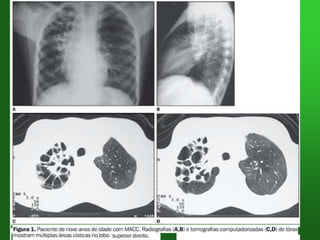

NEUMONIA LOBAR +ATELECTASIA